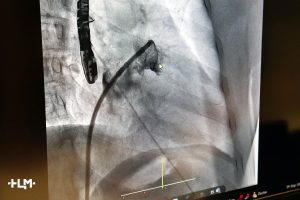

Операции были выполнены с применением современной малоинвазивной методики. Через небольшой прокол в бедренной вене хирурги под рентгенологическим и ультразвуковым контролем провели катетер в полость сердца и установили в ушко левого предсердия специальное устройство – окклюдер (Watchman). Это миниатюрное устройство, напоминающее зонтик, надежно изолирует ушко от основного кровотока, предотвращая образование тромбов.